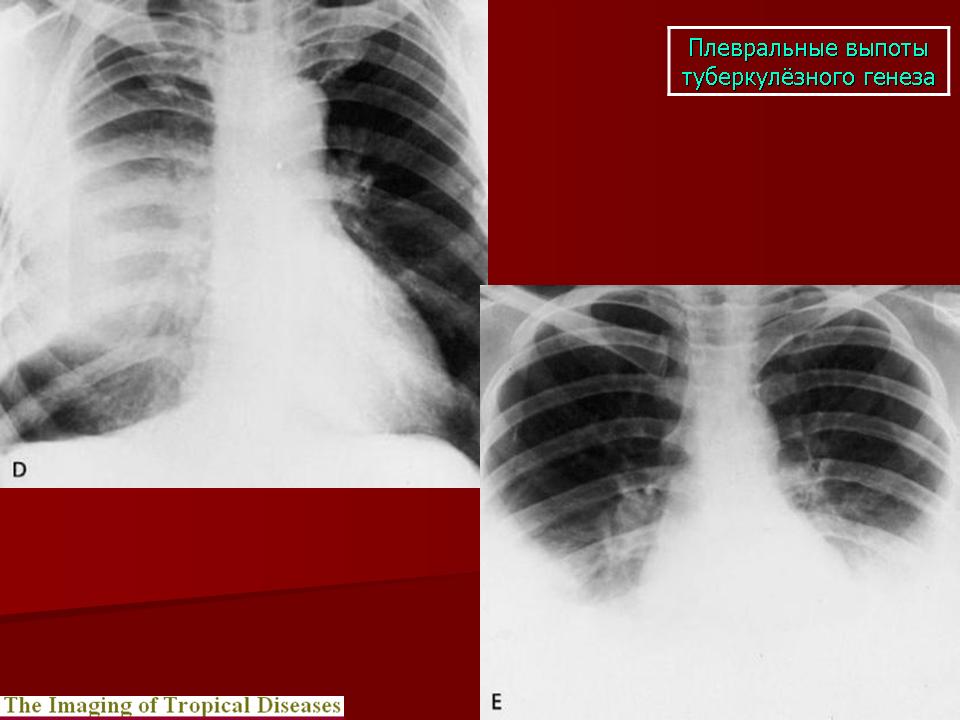

Продолжение.

Приложения:

slayd192mm.jpg